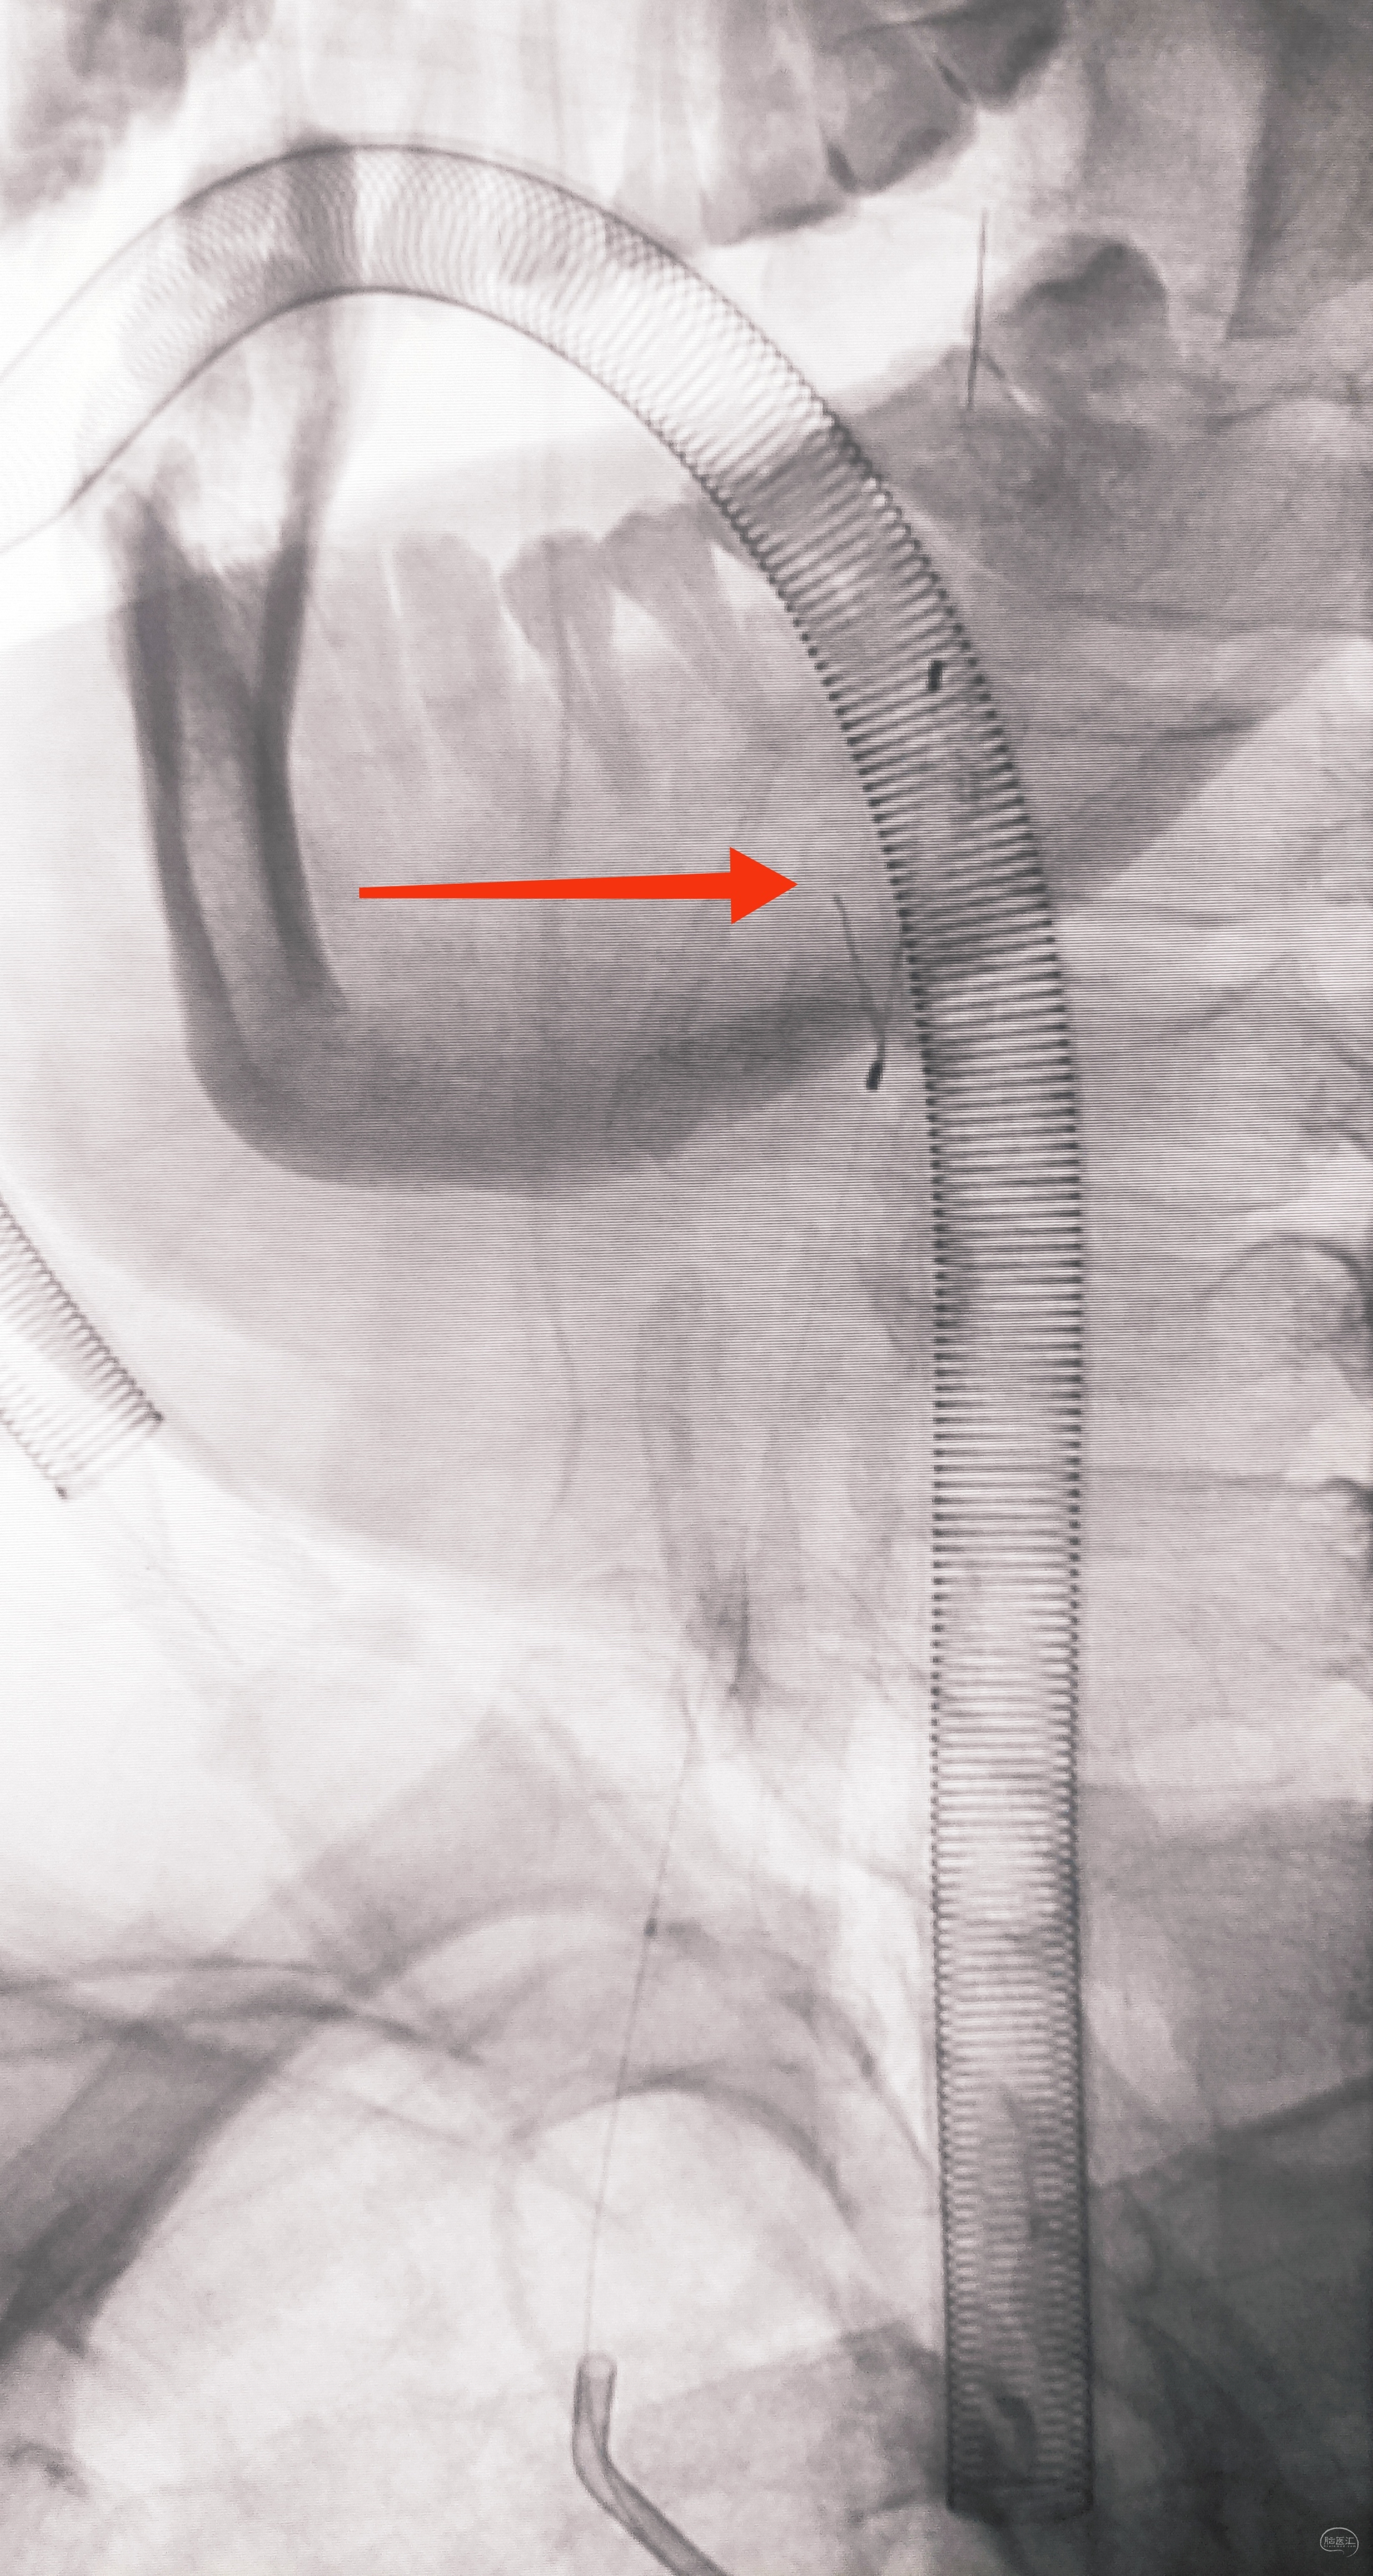

因为是极重度狭窄,支架前拟小球囊预扩,谨慎起见,置入泰杰Proender保护伞并打开,以免不测

梯度预扩,先雅培1.5×15小球囊预扩

再Sino3×20球囊预扩

预扩满意,保护伞不浪费,借助保护伞的支撑和保护作用,上送导引导管(不怕掉斑块,物尽其用),为颅内狭窄处理提供更佳支撑

看图说话,没啥聊的。球囊不浪费,Sino3×20球囊预扩V4狭窄

EP4.5×22支架置入

导引导管保持原位,导管内安全输送Herculink5×20,通过椎开口狭窄并走远,再回撤导引导管至锁骨下动脉

球扩支架顺利释放